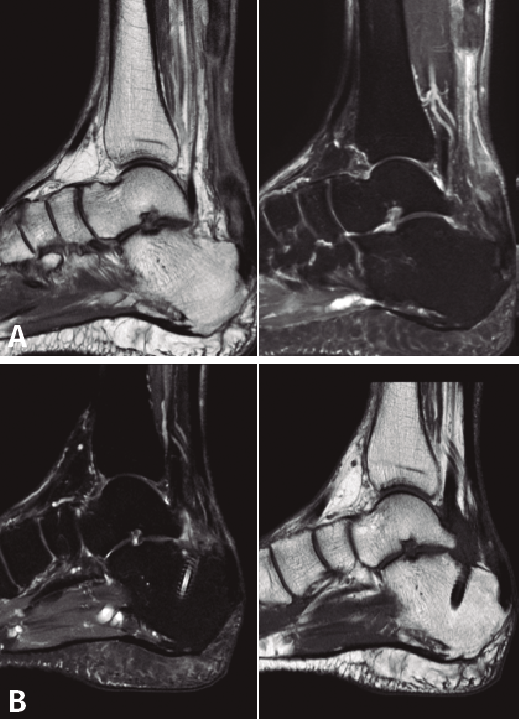

A todos los pacientes se les realizó una radiografía simple, sin detectar ninguna lesión ósea, y una resonancia magnética (RM) preoperatoria para demostrar la existencia de una rotura completa del TC, poder medir el defecto existente y evaluar el estado del FHL previo a la transferencia, y las posibles variantes anatómicas que puedan facilitar o dificultar la técnica quirúrgica descrita. Finalmente, se realizó una RM postoperatoria a todos los pacientes, a los 9-12 meses después de la cirugía, para ver la correcta integración del FHL en el calcáneo y la posible reparación del TC.

La RM preoperatoria mostró una rotura completa del TC y la retracción proximal del tendón en todos los casos, con un defecto medio de 75 mm (mediana: 76; rango: 65-85 mm). No se observó patología del tendón de FHL u otras anormalidades en ninguno de los pacientes.

Posteriormente, a todos pacientes se les realizó una RM postoperatoria a los 9-12 meses, para observar la correcta integración de la plastia en el túnel del calcáneo. En todos los casos se objetivó la reparación del defecto del TC, lo cual lo atribuimos a la aposición del vientre muscular del FHL y a la carga en ausencia de estrés mecánico (Figura 5).

En nuestro estudio, fue especialmente relevante la mejoría de la puntuación media de la escala AOFAS, la cual aumentó de 35 antes de la operación a 87 puntos postoperatoriamente de media. Todos los pacientes volvieron a sus actividades previas a la lesión, sin presentar limitaciones ni complicaciones derivadas de la técnica quirúrgica. A su vez, es también relevante el fenómeno de reparación del TC que se pudo observar en todos los pacientes en la RM postoperatoria. Este fenómeno se cree que se debe al aporte vascular que supone aproximar el vientre muscular del FHL al realizar la transferencia tendinosa, junto con la carga en ausencia de estrés mecánico.